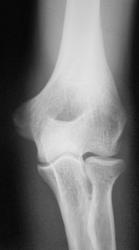

Перелом проксимальной1/3 лучевой кости.

Красивый перелом, только не срастется-головку резецируют.

Вколоченый внесуставной перелом шейки лучевой кости.Гипсовая иммобилизация в течение двух недель,потом шарнирный ортез.